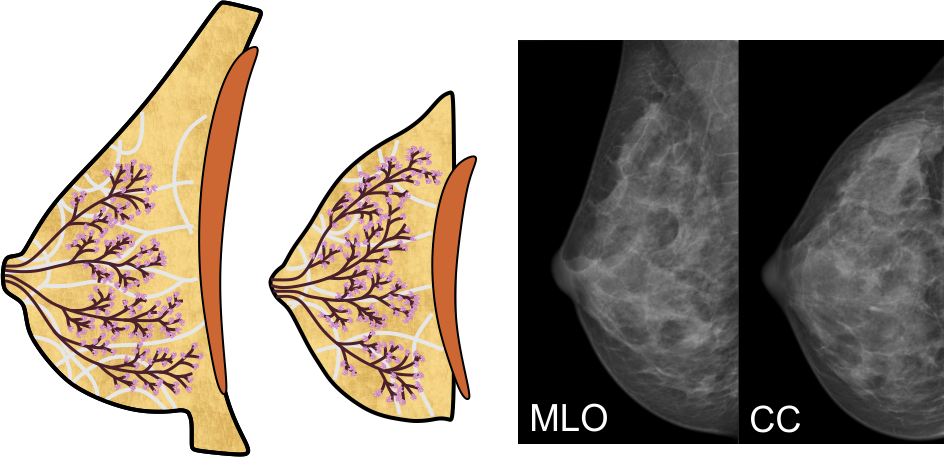

Aufbau der Brust

Die vier oben genannten Gewebearten sind in ihren Anteilen in jeder Brust individuell angelegt. Die meisten Frauen haben eine ausgewogene Verteilung, bei manchen kann jedoch eine bestimmte Gewebeart überwiegen. Dazu verändert sich die Brust mit zunehmendem Alter, die Milchgänge und das Bindegewebe werden vor allem nach dem Wechsel dünner, die 'Blätter' des Baums 'verwelken' - die Drüsenläppchen schrumpfen also, und der Fettgewebeanteil wird größer. Üblicherweise entwickeln sich diese Veränderungen von innen nach außen, und von unten nach oben.